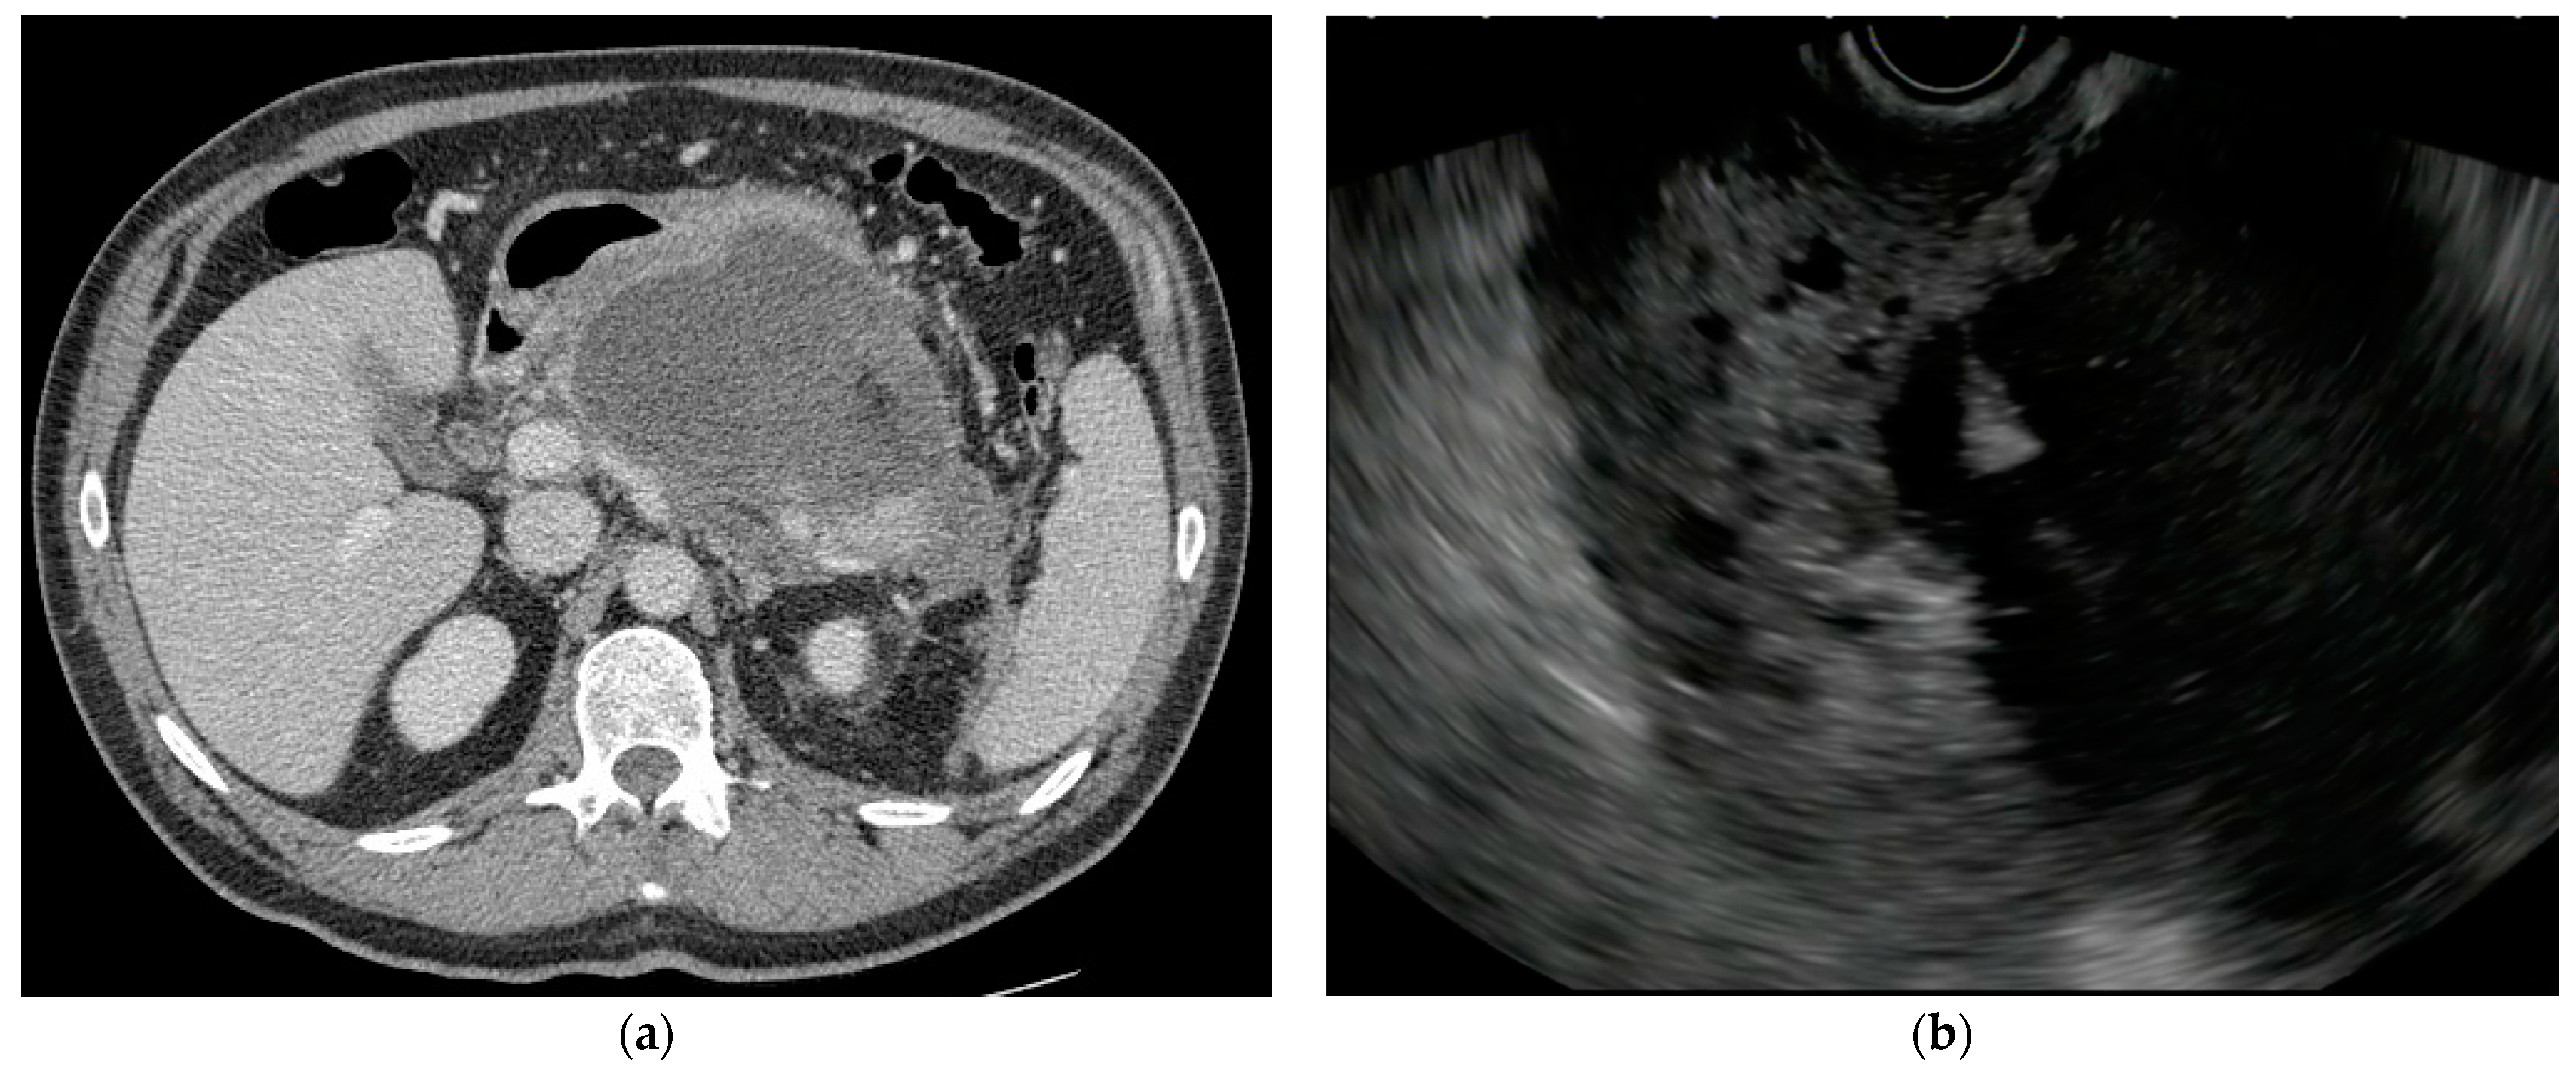

5. Evolution in Endoscopic Drainage Techniques